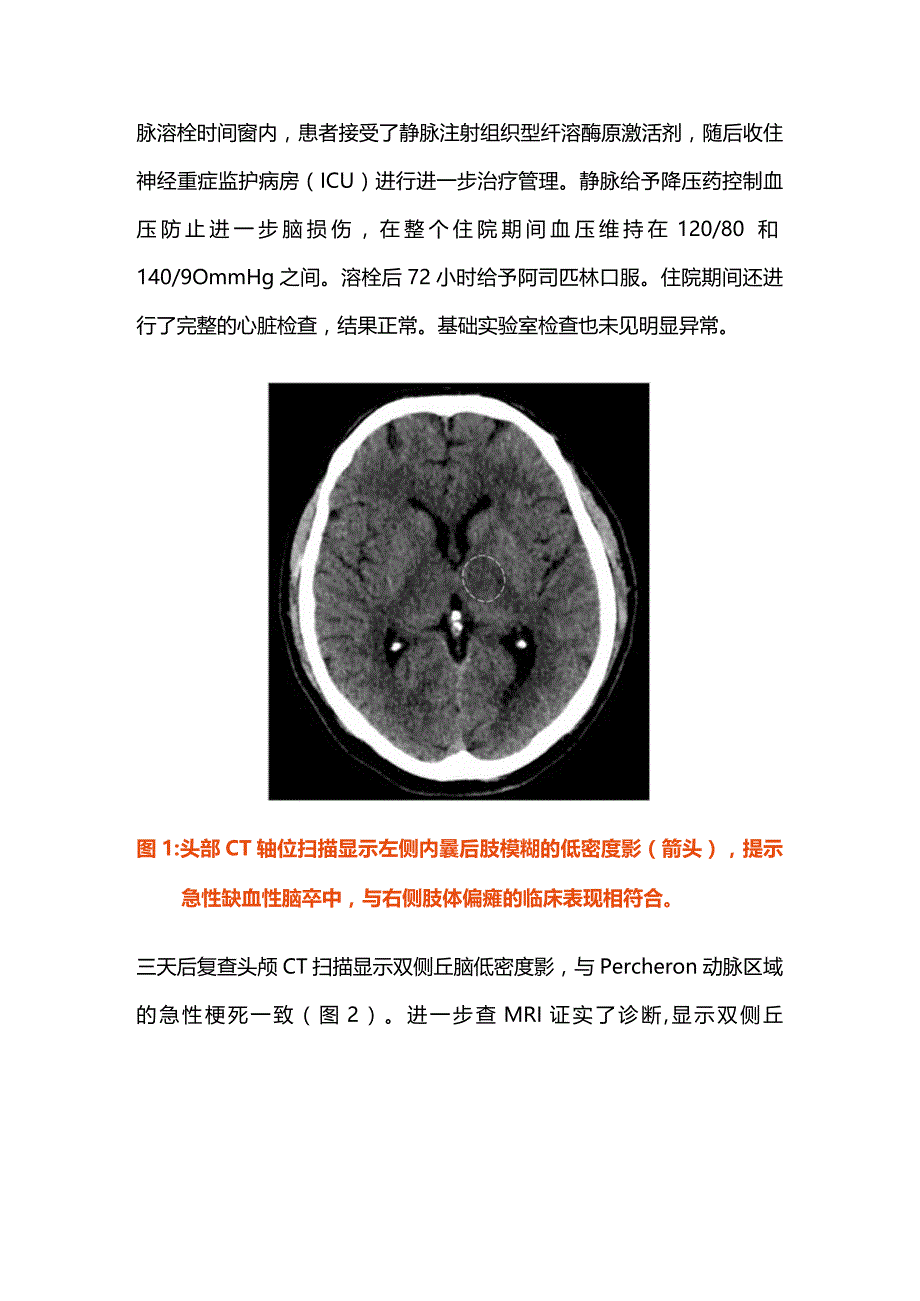

2、8岁女性的病例,患者主因突然出现的意识错乱、说话困难和右侧肢体无力持续一小时而来到急诊室。既往高血压和高血脂病史,在就诊时没有服用任何药物。在检查时她判断能力下降,格拉斯哥昏迷量表评分为12/15,右侧肢体偏瘫,美国国立卫生研究院卒中量表评分为12分,垂直凝视受损,轻度构音障碍,血压为180100mmHg,心率为90次/分。初始的非增强头部CT显示与右侧肢体偏瘫的临床表现相一致的左侧内囊后肢模糊低密度影,提示急性缺血性脑梗死(图1)。由于监测血压高于180/105mmHg,给与患者服用他汀类药物和抗高血压药物。由于发病在静脉溶栓时间窗内,患者接受了静脉注射组织型纤溶酶原激活剂,随后收住神经重症

3、监护病房(ICU)进行进一步治疗管理。静脉给予降压药控制血压防止进一步脑损伤,在整个住院期间血压维持在120/80和140/9OmmHg之间。溶栓后72小时给予阿司匹林口服。住院期间还进行了完整的心脏检查,结果正常。基础实验室检查也未见明显异常。图1:头部CT轴位扫描显示左侧内曩后肢模糊的低密度影(箭头),提示急性缺血性脑卒中,与右侧肢体偏瘫的临床表现相符合。三天后复查头颅CT扫描显示双侧丘脑低密度影,与Percheron动脉区域的急性梗死一致(图2)。进一步查MRI证实了诊断,显示双侧丘脑和中脑吻侧扩散受限,MRA提示单一动脉主干供应双侧旁正中丘脑(图3)。图2:冠状位CT头部图像显示双侧丘